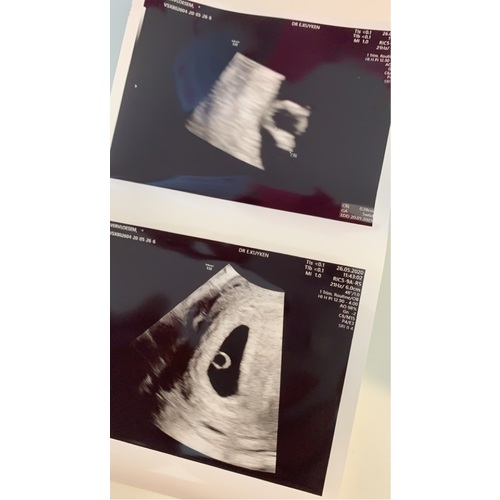

Dit was 5 weken ong en ik kon niet veel zien maar wel iets gelukkig 9 juni weer een echo hopen op een kloppende hartje